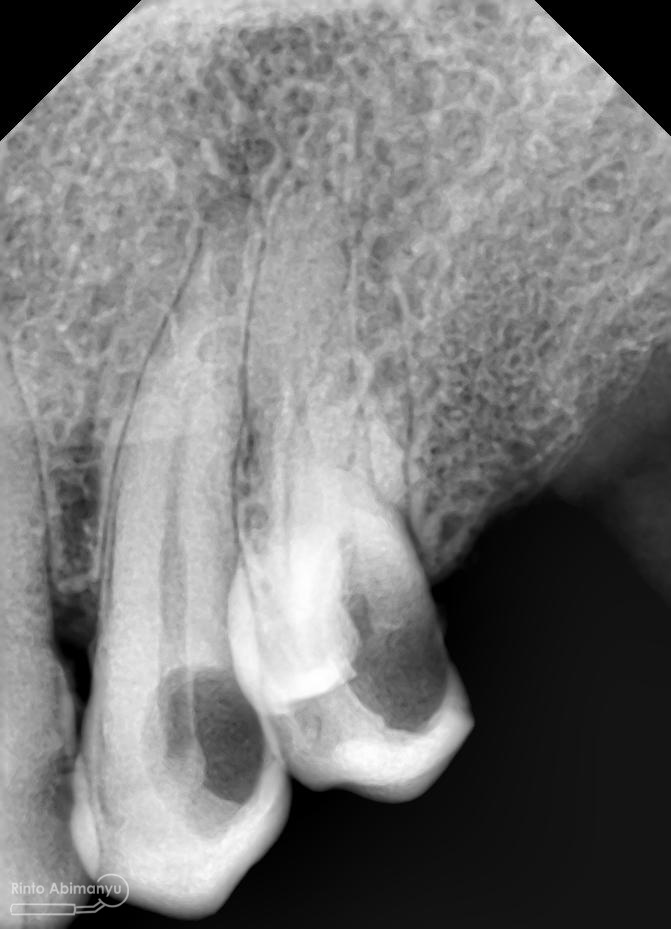

Pemeriksaan respon dingin pun menunjukkan hasil negatif, untuk menambah data dalam penegakan diagnosis maka dilakukan pengambilan ronsen pada gigi2 tersebut

Terlihat dari ronsen tersebut karies pada gigi 23 24 sudah mencapai pulpa… dari informasi pemeriksaan klinis dan ronsen maka didiagnosis gigi tersebut nekrosis.. Saya jelaskan kepada pasien mengenai kondisi gigi2 nya dan rencana perawatan yang akan saya lakukan…